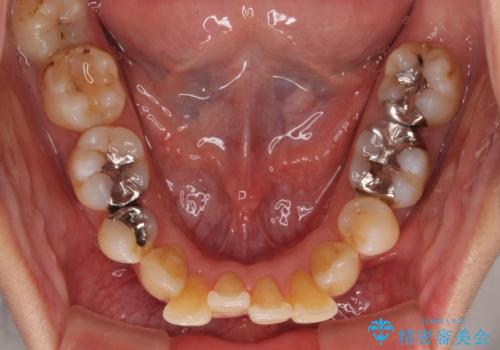

後戻りで突出した前歯をインビザラインで解消

- 抜歯矯正の後戻りで前歯が突出してきていることを気にして来院された患者様です。

口元の突出感を改善するにあたり、抜歯矯正は行うことができないため、奥歯の後方移動とIPR(歯と歯の間を削る)により達成することとしました。

再度後戻りしたときに対応しやすいよう、インビザラインにて矯正治療を行うこととしました。

舌の突出癖がなかなか改善できず、IPRによる前歯の隙間が閉じきらずに、予定よりも長い治療期間となりました。